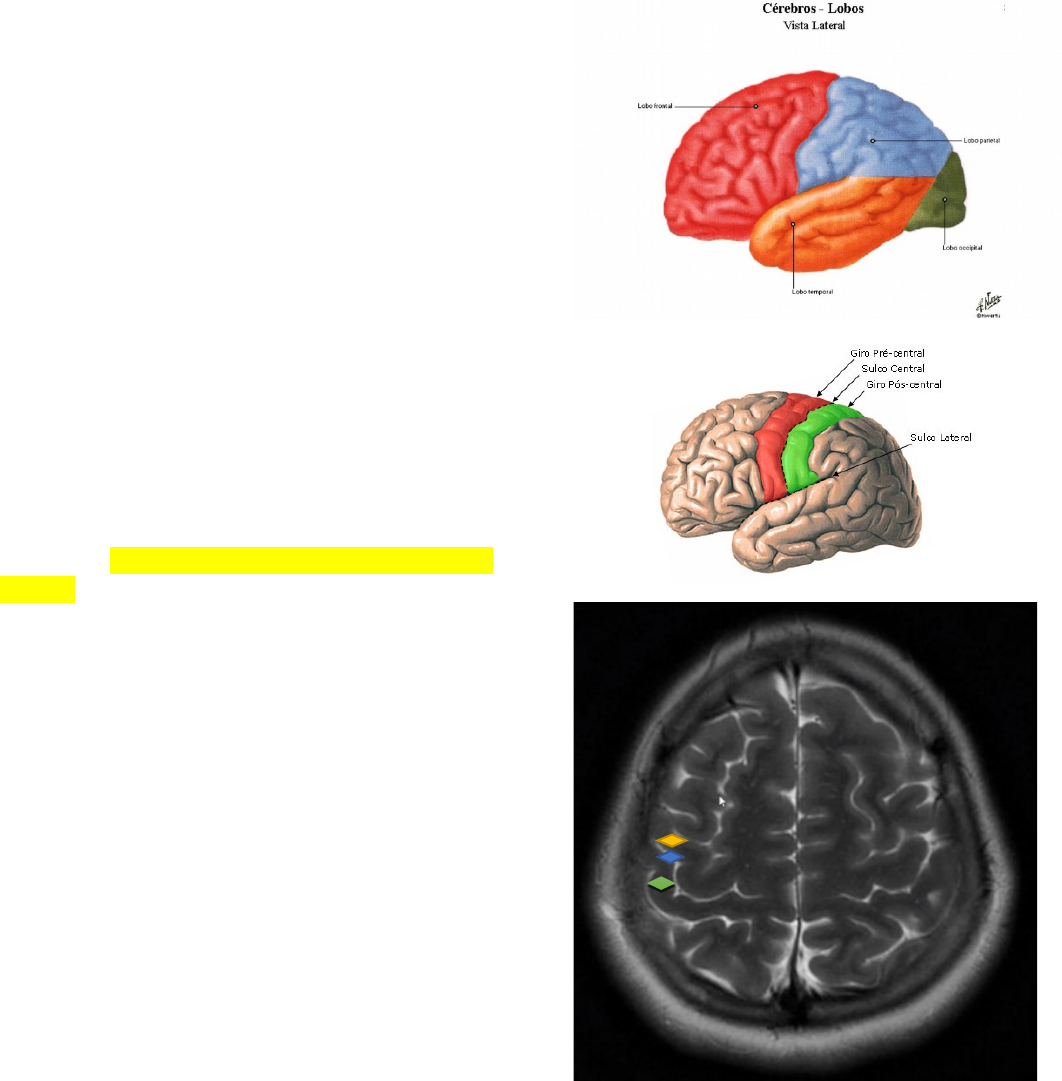

O telencéfalo inclui os hemisférios, separados pela fissura longitudinal, e os núcleos da base. Cada hemisfério é dividido em 4 lobos; cada lobo está relacionado com o osso subjacente de mesmo nome.

O sulco central separa os lobos frontais dos lobos parietais.

O sulco lateral separa o lobo temporal dos lobos frontais e parietais.

Entre o sulco central e o sulco pré-central temos o giro pré-central, onde se localiza a principal área motora do cérebro.

Entre o sulco pós central e o central tem-se o giro pós central, área de função sensitiva (área somestésica).

Giro pré central função motora

Sulco central sinal do ômega (área motora da mão)

Giro pós central função sensitiva – já faz parte do lobo parietal